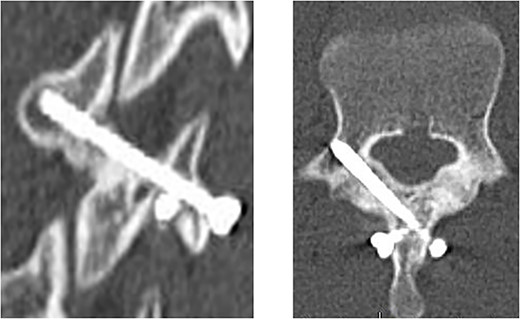

The postoperative course was uneventful, and he did not complain about low back pain. He started to walk 1 day after the surgery wearing a hard trunk brace. Jogging was allowed 1 month after the surgery. Two months after the surgery, CT scans showed sufficient bone union and he started sprinting and twisting his lower spine (Fig. 5). Finally, he returned to javelin throwing without any pain and took part in a national competition 12 months after the surgery.

CT scan at 2 months after surgery; oblique view (left panel) and horizontal view (right panel).